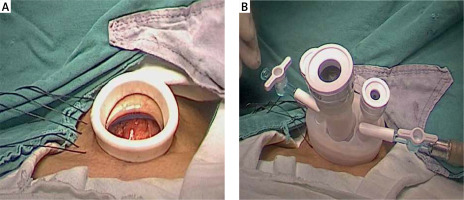

An initial 2.5 cm collar incision is made about 2 fingers above the suprasternal notch. The incision may be extended to up to 3.0 cm later if necessary. A natural deep skin crease is preferable if present. The platysma is divided. The subplatysmal space is developed to the thyroid cartilage superiorly and the suprasternal notch inferiorly. The cervical linea alba is divided longitudinally. The strap muscles are separated from the thyroid lobe. The isthmus is divided and dissected off the trachea. A working space for single-port endoscopic surgery is constructed just under the platysma muscle or strap muscles. The method to construct the working space under the platysma is as follows: Two or 3 percutaneous stay sutures penetrating the strap muscles are placed for retracting the strap muscles laterally to expose the thyroid. The internal anchoring ring of the retractor component of the single multi-channel port is inserted into the operative site under the platysma. One should carefully check to ensure that no tissue entrapment has occurred. The external retraction ring is gently grasped and pulled up until the internal anchoring ring sits tightly against the platysma. The external ring is flipped inward until desired retraction is achieved, then the valve component of the single multi-channel port is connected with the external ring (Photo 2). The working space is maintained with low pressure carbon dioxide insufflation at 4–6 mm Hg and flow rate of 6 l/min. The method to construct the working space under the strap muscles is similar to that under the platysma; however, the percutaneous stay sutures are not required, and the internal anchoring ring of the retractor component of the single multi-channel port is inserted into the operative site under the strap muscles.

Photo 2

Setup of the single multi-channel port. A – Desired retraction of the incision achieved with the wound retractor component. B – The valve component connected with the external ring of the wound retractor component